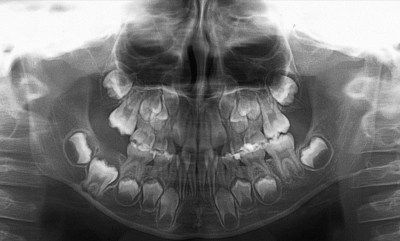

7歳の男児。歯の萌出遅延を近医で指摘され来院した。初診時の口腔内写真とエックス線写真を別に示す。

今後予想されるのはどれか。1つ選べ。

a. 上顎側切歯の高位

b. 下顎犬歯の早期萌出

c. 上顎右側第一大臼歯の挺出

d. 下顎右側第二大臼歯の遠心傾斜

e. 下顎右側第二乳臼歯の晩期残存